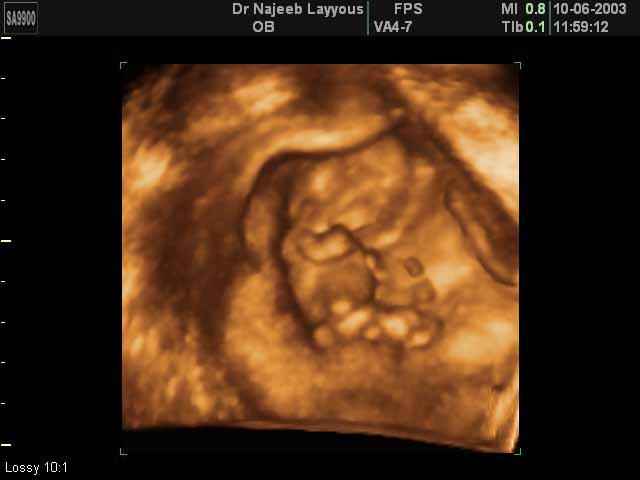

- First Trimester Ultrasound Photos

3D First Trimester Ultrasound Scan Photos ( Early Pregnancy Ultrasound Photos ) | Dr N Layyous